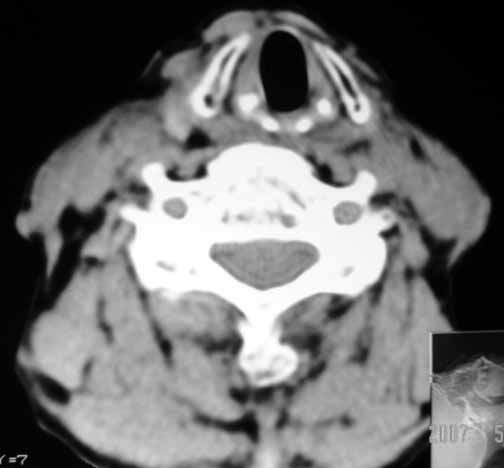

以下是引用jw-830在2007-5-24 15:33:00的发言:[br]右侧甲状腺增大,内可见低密度,病灶与周围软组织界线欠清晰,建议增强扫描除外甲状腺癌

以下是引用adams在2007-5-24 17:15:00的发言:[br]支持“ 右侧甲状腺增大,内可见低密度,病灶与周围软组织界线欠清晰,建议增强扫描除外甲状腺癌”。 [br] [br] [br][br] [br] [br]

以下是引用苯小孩在2007-5-24 15:26:00的发言:[br]左侧甲状腺腺癌或瘤,建议穿刺或核素进一步检查.